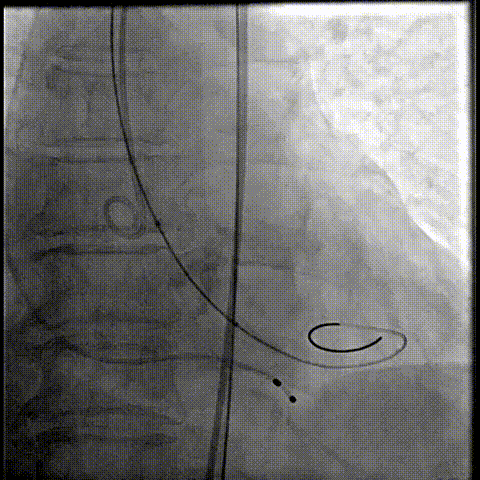

释放瓣膜

80%工作位评估

23球囊后扩

最终造影形态位置良好,轻微瓣周漏